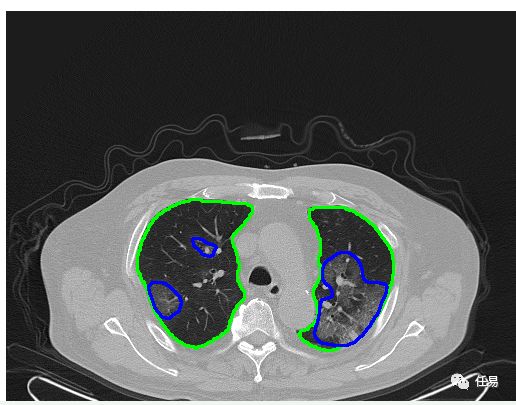

2020年跟古代的最大不同,是我们多了人工智能AI技术。AI识别CT的原理,其实就是把图片进行切割,然后进行卷积,识别边缘,包括识别颜色,就是我们熟知的大白肺,所以只要有了足够的、经过标注的图像数据,我们就能用AI识别出来。

仅仅诊断CT还不够的话,AI还可以根据位置大数据、流行病学史、患者症状这类关键词辅助诊断,这样准确度可以进一步提升,帮助武汉做到应收尽收,全力抗疫。